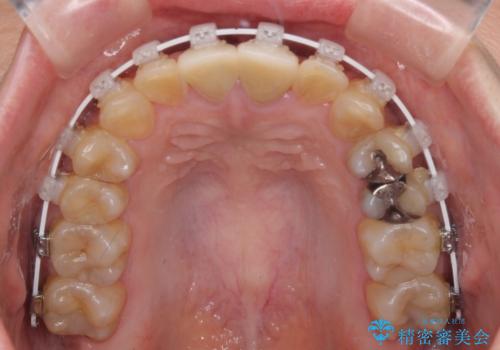

- 矯正装置

- 審美装置

抜歯矯正により口元を引っ込めることも検討しましたが、特に口元の突出感は気になっていないとのことで、非抜歯にてワイヤー装置で矯正治療を行うこととしました。